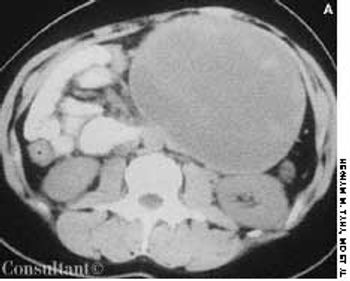

A 24-year-old woman was concerned about a protruding epigastrium mass that had grown since it was first noted 4 months earlier. She had no abdominal pain, nausea, or vomiting.